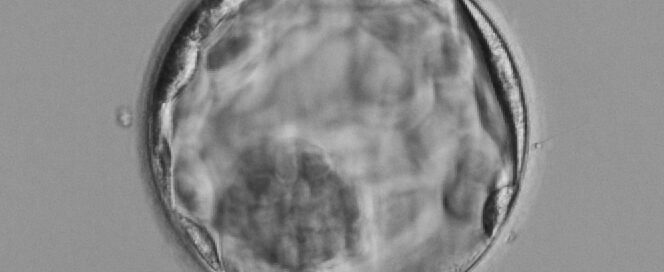

Embryo – dess utveckling

De två cellerna som ska bilda embryot är från början två helt separata könsceller, ett ägg och en spermie. Vid befruktningen smälter de samman och deras DNA (arvsanlag) bildar en gemensam cellkärna. Efter många celldelningar, utveckling och tillväxt bildas en fungerande människa. Det är en komplicerad process och det är inte konstigt att detta tar [...]